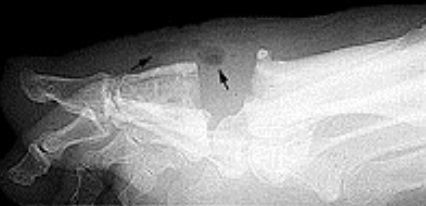

| What disease is this? What do the arrows indicate? | Gout Arrows = 'punched out' erosions |

| What disease is this? What indicates this? | Tophaceous gout. Soft tissue swelling surrounding the index finger PIPJ, with associated erosion and bone resorption |